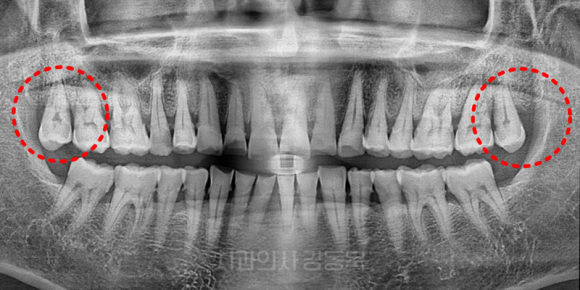

위쪽 사랑니

위쪽 사랑니는 그래도 쉬운 거 아닌가요?

라고 궁금해하실 수 있는데요.

촬영일자: 2024.07.24

위 사랑니 이해를 돕기 위한 참고 사진입니다.

물론 아래쪽 사랑니보다야

수월한 경우가 많겠지만

뿌리 형태나 위치, 주변 구조 등에 따라

난이도가 달라질 수 있는데요.

그래서, 무조건 쉽다고 단정 지을 수는 없습니다.